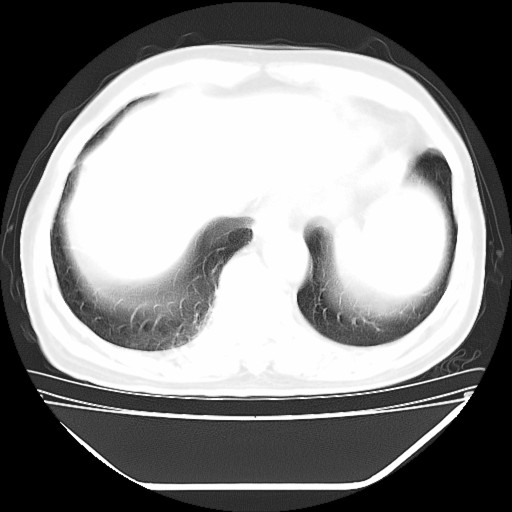

以下是引用hhcckk在2009-5-29 10:34:00的发言:[br]左下肺片絮状边缘模糊影,考虑感染,建议治疗后复查[br]